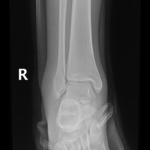

if the fracture is displaced, surgery may be needed to put the bone back into the correct position and fix the bone with Plates & screws or nails for adequate healing to occur.

- Ankle Fractures.